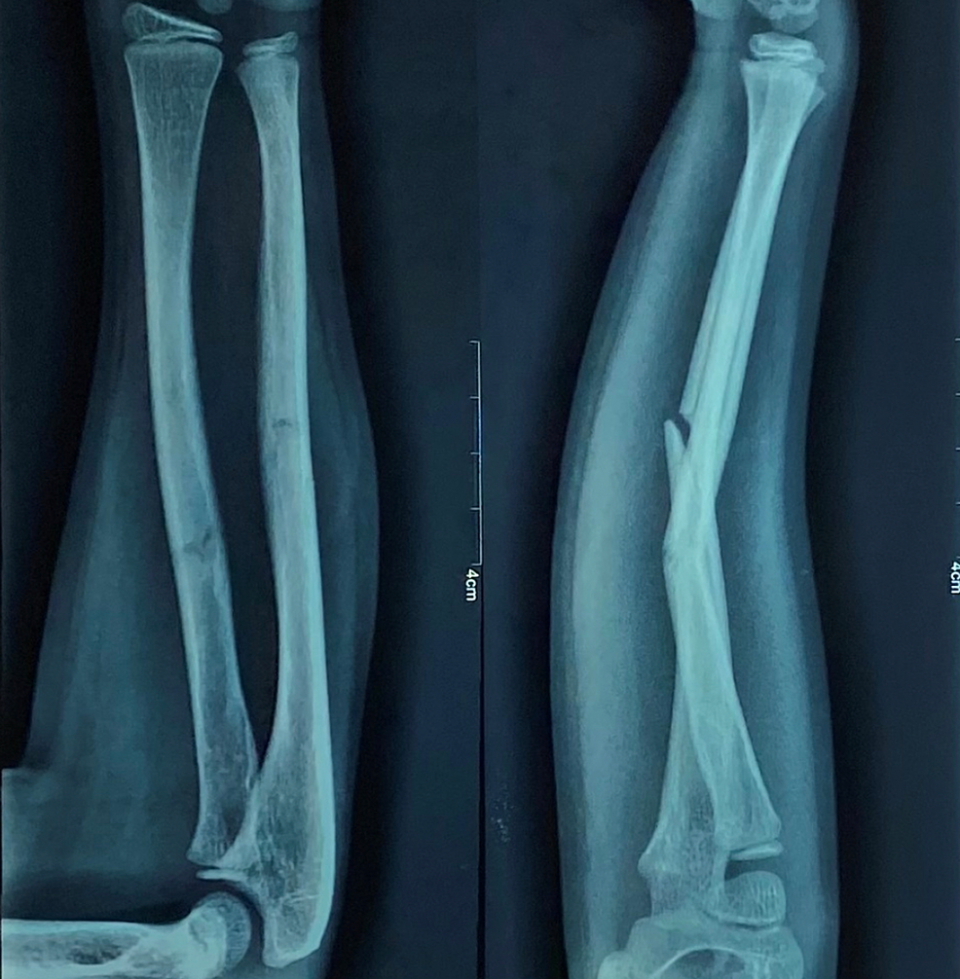

Pre-operative antero-posterior (AP) and lateral x-ray were taken (Figure 1). Adequate sedation was given to the patient. Fracture was reduced by the standard technique of axial traction manipulation. Reduction was confirmed radiologically by image intensifier and if found satisfactory, cast application was done (Figures 2, 3).

The above-elbow cast was put after proper padding, with elbow joint in extension and forearm in the most stable position (Figure 4). A cast index = 0.7 or less, calculation of which was done by dividing inner sagittal width of cast by inner coronal width of cast at fracture level, decreases fracture re-displacement risk. If reduction was not found to be acceptable, the process was repeated under general anesthesia with the help of a C-arm.